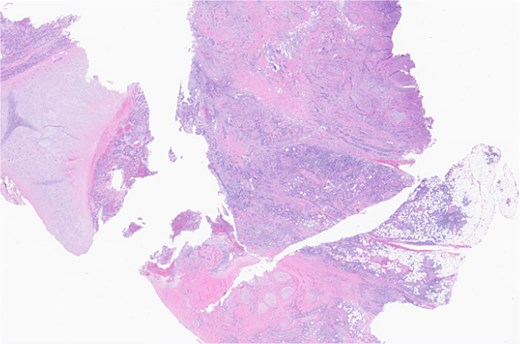

Subsequent surgery included left partial auriculectomy, wide local excision, and lateral temporal bone resection. Pathology revealed lymphatic invasion (LVI), perineural invasion (PNI), and facial nerve and mastoid bone involvement (Figs 4 and 5). CLL-fluorescence in situ hybridization (FISH) revealed 13q deletion; Immunoglobulin Heavy Chain gene (IGH) somatic hypermutation analysis identified IGHV3–23*01 rearrangement (mutated level 5.7%). Due to prior radiation, six cycles of cemiplimab were planned. A follow-up PET-CT scan showed enlarged, FDG-avid cervical lymph nodes and soft tissue nodularity beneath the posterior margin of the graft.

Facial nerve, left, proximal margin, biopsy: focally involved by invasive SCC.

Ear, left, auriculectomy: invasive moderately differentiated SCC, forming a poorly demarcated infiltrating dominant mass, ~5.5 cm in size and 2 cm in depth of invasion; extensive nerve invasion and focal lymphovascular invasion.